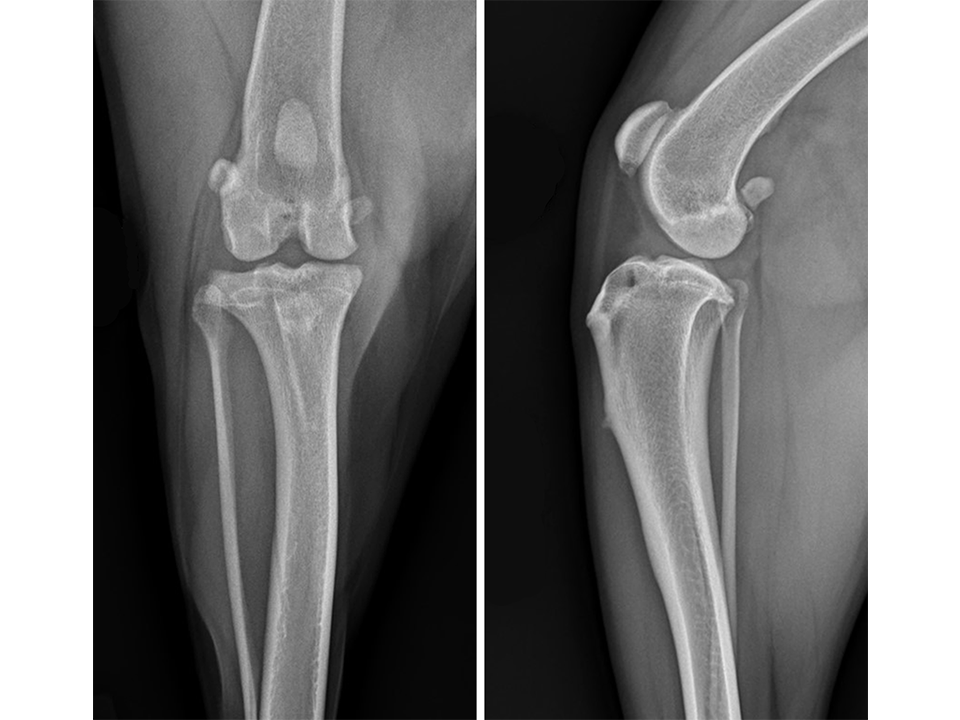

Radiographs of both stifle joints (Fig 5 and 6) revealed bilateral moderate joint effusion and minimal bony proliferation along the distal aspect of the patella. Considering the clinical findings, these radiographic signs were interpreted as minimal bilateral osteoarthritis secondary to CrCL disease.

The left stifle was evaluated for a Tibial Tuberosity Advancement (TTA) and the owner was advised that stabilization of the right stifle would likely be required in the future. Preoperative TTA planning was conducted using anatomic tibial plateau and patellar tendon angle landmarks. A 13.5 mm wedge and a size 6 plate were selected.